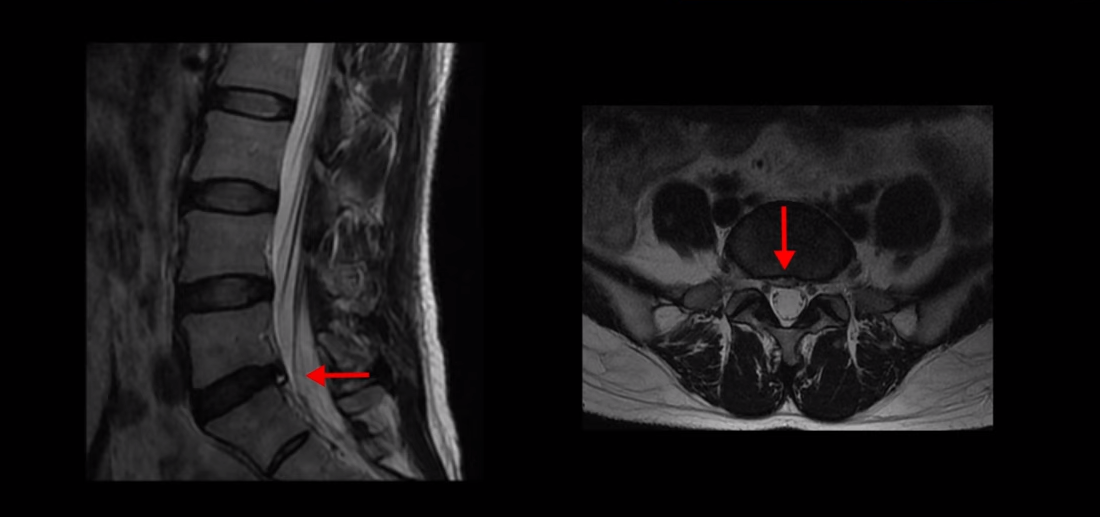

이 환자분은 앉기만 하면 바로 허리와 엉덩이가 심하게 아프고 양쪽 다리가 앉아도 저리고 일어서도 저리고 문제는 누워 있어도 다리가 저립니다. 이분 MRI를 보실까요?

보시다시피 퇴행성 디스크가 있고 디스크 밀려 나온 게 아주 조금 보이기는 하지만 신경을 눌러서 심한 방사통을 일으킬 정도로 특히 양쪽 다리가 앉아도 서도 누워도 저릴 정도로 심하지 않습니다. 이렇게 디스크가 심해 보이지 않으면 허리, 엉덩이 통증과 양쪽 다리 저림 증상의 원인을 다른 원인, 특히 근육으로 의심해 봐야 하는데도 진료 받은 대부분의 정형외과, 신경외과, 통증의학과에서는 근육 문제는 얘기하지 않고 디스크 문제만 얘기하고 치료합니다.

이분의 증상과 MRI를 비교해 봐도 신경 문제가 아니라는 건 명확합니다. 일단 저렇게 가벼운 디스크 탈출이 심한 양쪽 다리 증상을 일으키기도 어렵고, 더군다나 디스크로 인한 신경 눌림은 일반적으로 누우면 줄어드니까 누워있으면 다리 저림이 조금이라도 줄어야 하는데 누워 있으면 오히려 더 심해집니다.

이 근육성 방사통이나 좌골신경통의 특징이 증상이 심한 사람들일수록 오히려 누워 있을 때 발끝까지 저린다고 하는 분들이 많습니다. 일반적인 디스크 증상과는 다른 증상입니다. 이렇게 MRI와 환자의 증상이 일치하지 않는데도 MRI에 보이는 아주 조그만 디스크 문제만 계속 치료하는 이유는 근육이 다리 저림을 일으킨다는 것을 인정하지 않는 의사들이 너무나 많기 때문입니다.